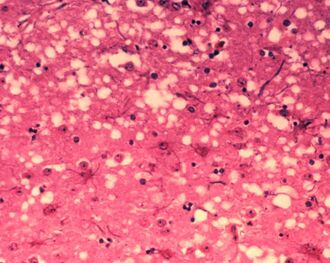

Brain tissue of a cow with BSE showing the typical microscopic "holes" in the grey matter

Diagnosis of BSE continues to be a practical problem. It has an incubation period of months to years, during which no signs are noticed, though the pathway of converting the normal brain prion protein (PrP) into the toxic, disease-related PrPSc form has started. At present, no way is known to detect PrPSc reliably except by examining post mortem brain tissue using neuropathological and immunohistochemical methods. Accumulation of the abnormally folded PrPSc form of PrP is a characteristic of the disease, but it is present at very low levels in easily accessible body fluids such as blood or urine. Researchers have tried to develop methods to measure PrPSc, but no methods for use in materials such as blood have been accepted fully.[by whom?]

The traditional method of diagnosis relies on histopathological examination of the medulla oblongata of the brain, and other tissues, post mortem. Immunohistochemistry can be used to demonstrate prion protein accumulation.[25]